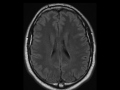

Grey Matter Heterotopia

33-year-old male with a history of recurrent seizures. On the coronal T1 and inversion recovery sequences, there is an ovoid focus within the periventricular white matter of the left frontal horn which is hypointense to surrounding white matter but isontense to the cortical grey matter. The nodule is also isointense to the cortical grey matter on the subsequent FLAIR and T2-weighted images. The findings are compatible with cortical grey matter heterotopia. Grey matter heterotopia results from the interruption of the normal neuronal migration from periventricular region to the cortex. Grey matter heterotopias can be subdivided into nodular heterotopias and diffuse heterotopias. The nodular heterotopias consist of subependymal heterotopia, this case, and sucortical heteroptopias. Diffuse heterotopias consist of band heterotopia, lissencephaly, and laminar heterotopia.